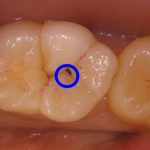

歯が欠けて物が詰まりやすい ダイレクトボンディングによる虫歯治療

治療前 治療後 性別 女性 相談内容 歯が欠けた カウンセリング・診断結果 プラ ...